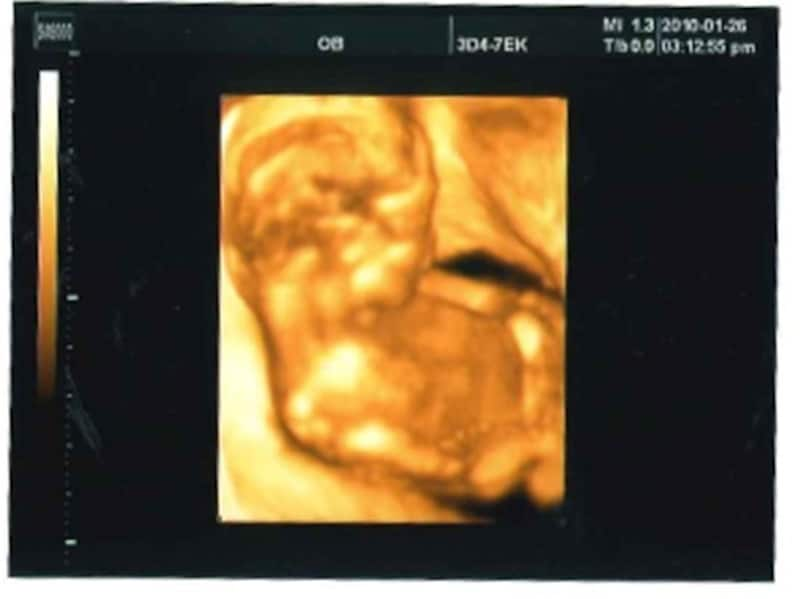

妊娠16週 赤ちゃんの性別が分かる人も!胎児の大きさ・エコー写真

妊娠17週目エコー写真・胎児の大きさ・胎動や性別が分かることも!

妊娠18週目エコー写真・赤ちゃんの大きさ・胎動が分かる人も

妊娠19週目 胎動や性別が分かる人も!胎児のエコー写真・大きさ